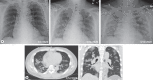

Novel coronavirus disease 2019 (COVID-19) is a highly infectious, rapidly spreading viral disease with an alarming case fatality rate up to 5%. The risk factors for severe presentations are concentrated in patients with chronic kidney disease, particularly patients with end-stage renal disease (ESRD) who are dialysis dependent. We report the first US case of a 56-year-old nondiabetic male with ESRD secondary to IgA nephropathy undergoing thrice-weekly maintenance hemodialysis for 3 years, who developed COVID-19 infection. He has hypertension controlled with angiotensin receptor blocker losartan 100 mg/day and coronary artery disease status-post stent placement. During the first 5 days of his febrile disease, he presented to an urgent care, 3 emergency rooms, 1 cardiology clinic, and 2 dialysis centers in California and Utah. During this interval, he reported nausea, vomiting, diarrhea, and low-grade fevers but was not suspected of COVID-19 infection until he developed respiratory symptoms and was admitted to the hospital. Imaging studies upon admission were consistent with bilateral interstitial pneumonia. He was placed in droplet-eye precautions while awaiting COVID-19 test results. Within the first 24 h, he deteriorated quickly and developed acute respiratory distress syndrome (ARDS), requiring intubation and increasing respiratory support. Losartan was withheld due to hypotension and septic shock. COVID-19 was reported positive on hospital day 3. He remained in critical condition being treated with hydroxychloroquine and tocilizumab in addition to the standard medical management for septic shock and ARDS. Our case is unique in its atypical initial presentation and highlights the importance of early testing.